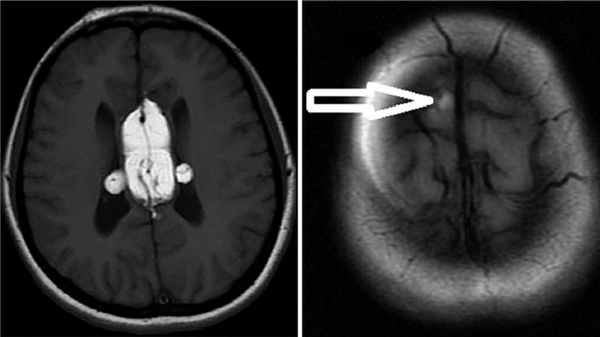

По данным магнитно-резонансной томографии имеют место гидромиелическая киста на уровне Th5-Th6, расщепление спинного мозга на два гемикорда ниже уровня Th7 (рис. 2). Прямых данных за компрессию спинного мозга нет. Деформация обладает значительным потенциалом прогрессии за счет поперечного дефекта передних структур. Первоочередной задачей хирургического лечения в настоящей ситуации является стабилизация позвоночника с дальнейшим рассмотрением вопроса о мобилизации и/или декомпрессии спинного мозга. Инструментальная фиксация не представляется возможной, так как на уровне порока отсутствуют пригодные к установке опорных элементов металлоконструкции как передние, так и задние структуры. Единственным применимым вариантом стабилизации является передний спондилодез без фиксации металлоконструкцией. Учитывая обусловленный отсутствием ригидной внутренней фиксации высокий риск несостоятельности костного блока, предпочтительно использование пластического материала, обладающего оптимальными прочностными, остеокондуктивными, остеоиндуктивными и остеогенными характеристиками. Принято решение выполнить спондилодез аутогенным реберным трансплантатом в сочетании с композитным материалом, состоящим из сульфата кальция (остеокондуктивная среда), деминерализованного костного матрикса (остеоиндуктивная среда) и аутогенного пунктата костного мозга (остеогенная среда).

Рис. 2. Предоперационная магнитно-резонансная томография: a — гидромиелическая киста на уровне Th5-Th6; b — расщепление спинного мозга на два гемикорда ниже уровня Th7